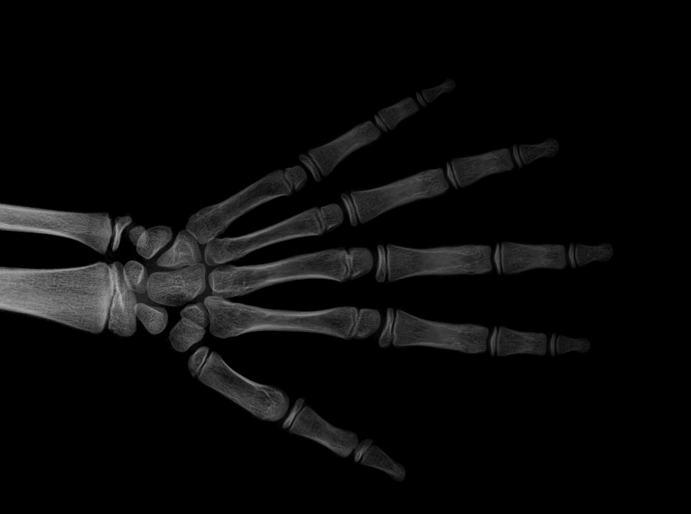

We performed three experiments for our method. First, we perform our method on several X-ray images, showing our method is not restricted by specific imaging objects. Second, we compared our method with image enhancement method and dehazing method, showing that our modification of the original dehazing indeed helps in this task. Third, we perform our method on a hand X-ray image dataset, showing its effectiveness and efficiency.

Several results from our method are shown in Fig. 7. The left column is the original input image. The right two columns are the soft tissue and bone image, respectively. It can be told that the soft tissue image is smooth as we assumed. Meanwhile, the bone image has better image contrast as desired. Moreover, our method can reach real-time performance on these X-ray images. The running time of our method on these images is reported in Table I.

Refer to caption

(a) original

(b) soft tissue

(c) bone (α=1.34𝛼1.34\alpha=1.34)

(d) original

(e) soft tissue

(f) bone (α=1.08𝛼1.08\alpha=1.08)

(g) original

(h) soft tissue

(i) bone (α=1.42𝛼1.42\alpha=1.42)

(j) original

(k) soft tissue

(l) bone (α=1.49𝛼1.49\alpha=1.49)

Figure 7: More results by our method. Input X-ray images (left), our estimated soft tissue (middle) and estimated bone image (right).